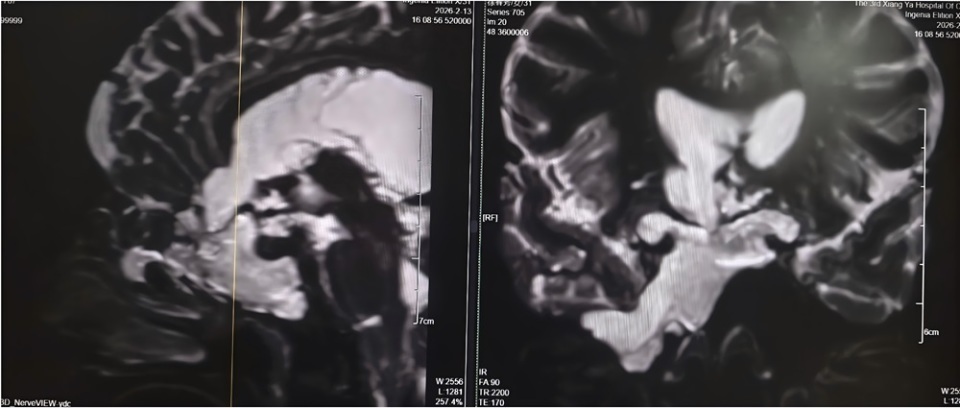

4年前,刘女士开始出现鼻腔流血、反复清水样流液,并伴有嗅觉减退。期间,她曾辗转多家医院及诊所就诊,医护人员多以“炎症”为病症进行对症治疗,但症状始终未得到根本改善。此后,刘女士多次出现发热伴鼻腔流液的情况,却一直未能明确病因,病情反复迁延。2026年2月11日,刘女士病情突然恶化,突发高热,体温超过39℃,并出现神志模糊的症状。当地医院紧急诊断后,确诊其为“脑脊液鼻漏合并颅内感染”,并下达了病危通知。危急时刻,家属紧急将刘女士转送至湘雅三医院功能神经外科求治,寻求进一步救治。 刘女士入院后,湘雅三医院功能神经外科杨靓副主任医师团队第一时间为其完善影像及实验室检查。经系统评估与综合分析,专家团队明确诊断刘女士所患疾病为——与脑室相通的高流量脑脊液漏,且其颅内感染情况较为严重。

团队指出,此类高流量脑脊液漏病情复杂,治疗难度极高:若直接进行修补手术,术后极易因颅内压力过高导致修补失败;同时,若在感染未充分控制前贸然封堵漏口,可能因失去引流通道导致颅内压骤升,进而造成病情急剧恶化,甚至危及患者生命。 为确保治疗安全有效,经多学科讨论后,杨靓主任团队为刘女士量身制定了“先引流控制感染,后精准修补漏口”的阶梯式治疗方案,分阶段推进救治工作,最大限度降低治疗风险。

2月14日,杨靓主任团队为刘女士实施“脑室—腹壁外引流术”,通过手术将其颅内感染的脑脊液引流至体外,同时联合规范的抗生素治疗,双管齐下控制感染。据悉,脑室—腹壁外引流术是一种临时的微创脑脊液引流手术,可快速降低颅内压力、廓清感染脑脊液,为后续根治性手术创造条件。经过持续引流和脑脊液更新,刘女士的感染症状迅速得到控制,体温逐渐恢复正常,意识也逐步清醒,病情趋于平稳。

2月26日,在确认刘女士颅内感染完全控制、身体条件达到手术标准后,杨靓主任团队为其开展经鼻内镜脑脊液漏修补术。术中,专家团队借助高清内镜的精准视野,准确定位漏口位置,同时从刘女士大腿取少量自体组织,为其完成多层严密修补,实现精准“堵漏”。据了解,经鼻内镜脑脊液漏修补术具有创伤小、恢复快、并发症少的优势,已成为脑脊液鼻漏修补的优选方式之一。 术后第一天,刘女士鼻腔清水样流液的症状便完全消失,困扰其多年的头痛也明显缓解。经过后续规范的护理与康复治疗,刘女士身体恢复良好,于3月初顺利出院,彻底摆脱了困扰4年的病痛。